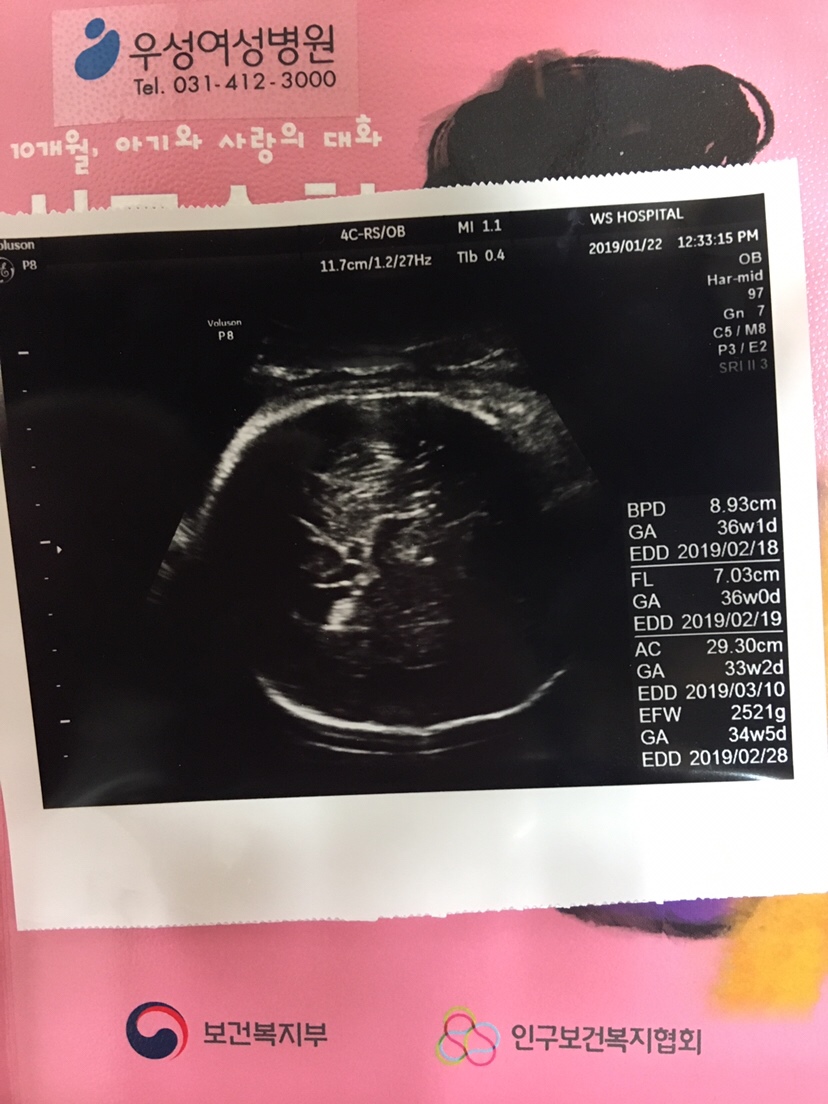

孕34周+0天

我上上次检查医生说我0.8到了1就是脑积水 都把我吓哭了,一个星期去复查 医生没说这个事,都说后期宝宝会自己吸收 愿我们的宝宝健健康康

@乖乖*~宝[帖主]:月份这么大了不好吸收了吧?你的0.8厘米,没超过1厘米,没事的。可我的就不一样了,我的是超过了1厘米,而且是从0.82扩张到1.1,所以我很担心。

李洋:我媳妇39周检查,突然说1.1,之前一直都检查很好,都不知道因为啥突然会这样!